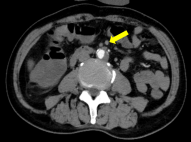

68岁,男性,突发剧烈腹痛10小时,陈旧性心肌梗死、心房颤动,曾在外院按照急性胆囊炎诊治,因腹痛明显加重来我院急诊。行开腹探查+肠系膜上动脉取栓术。

67岁患者,突发下腹痛2天,既往房颤未系统治疗,全腹增强CT提示肠系膜上动脉血栓、肠梗阻。

全腹持续性腹痛2天;诊断:肠系膜上动脉(分支)闭塞、脾梗死、房颤和弥漫性腹膜炎;查体:全腹压痛、反跳痛伴肌紧张,右侧下腹部腹痛较重;行右半结肠切除术、肠系膜上动脉取栓术,术后经历感染休克关,现患者恢复良好,于血管外科病房治疗中。